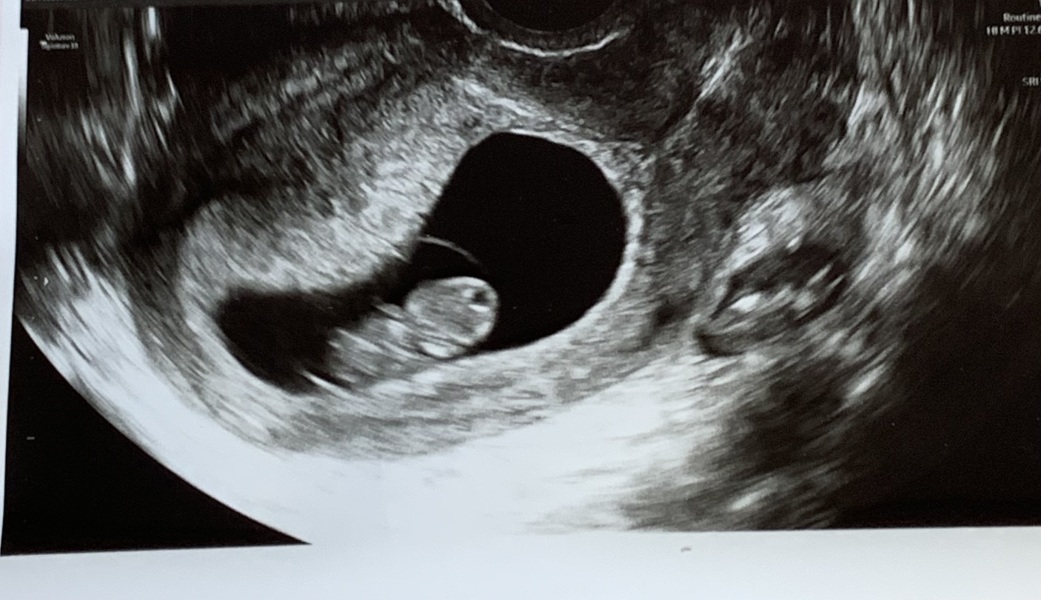

Can anyone tell me if this looks like a single ot twin pregnancy

I had a scan the other but come home and lots of people saying whats that in the sac next to it looks like little legs or something can anyone help me with this please ?

That is likely a fibroid

It's not within your uterus so very unlikely to be another fetus, could be your bladder, ovary or like pp mentioned fibroid.